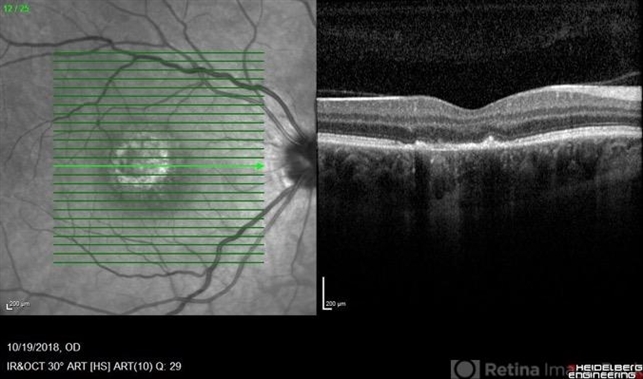

- A 37-year-old female presented with a two-week history of vision loss in the right eye. She experienced a flu-like illness including rash on the hands, feet, and mouth 2 days prior to her vision change. Her 3-year-old son had a similar illness diagnosed as hand, foot, and mouth disease by his pediatrician one week prior. Her visual acuity was 20/150 of the right eye, and 20/20 of the left eye. On dilated fundus examination, the left eye was unremarkable; the right eye revealed a circular, variably pigmented lesion of the macula. OCT imaging showed areas of RPE loss and clumping, with overlying loss of the photoreceptor layer. Fluorescein angiography showed central and peripheral hyperfluorescence consistent with window defect, and blockage in area of RPE loss. No treatment was initiated at this time. The patient returned 10 days later; her visual acuity improved to 20/50 in the right eye. Dilated fundus exam showed increased pigmentation of the macular lesion. OCT of the right eye showed further RPE clumping without recovery of the photoreceptor layer, despite her improved visual acuity.